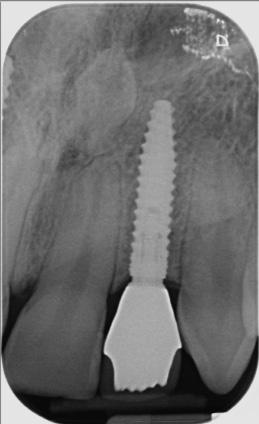

CASE STUDY

Guided implant approach for reproducible results, page 28